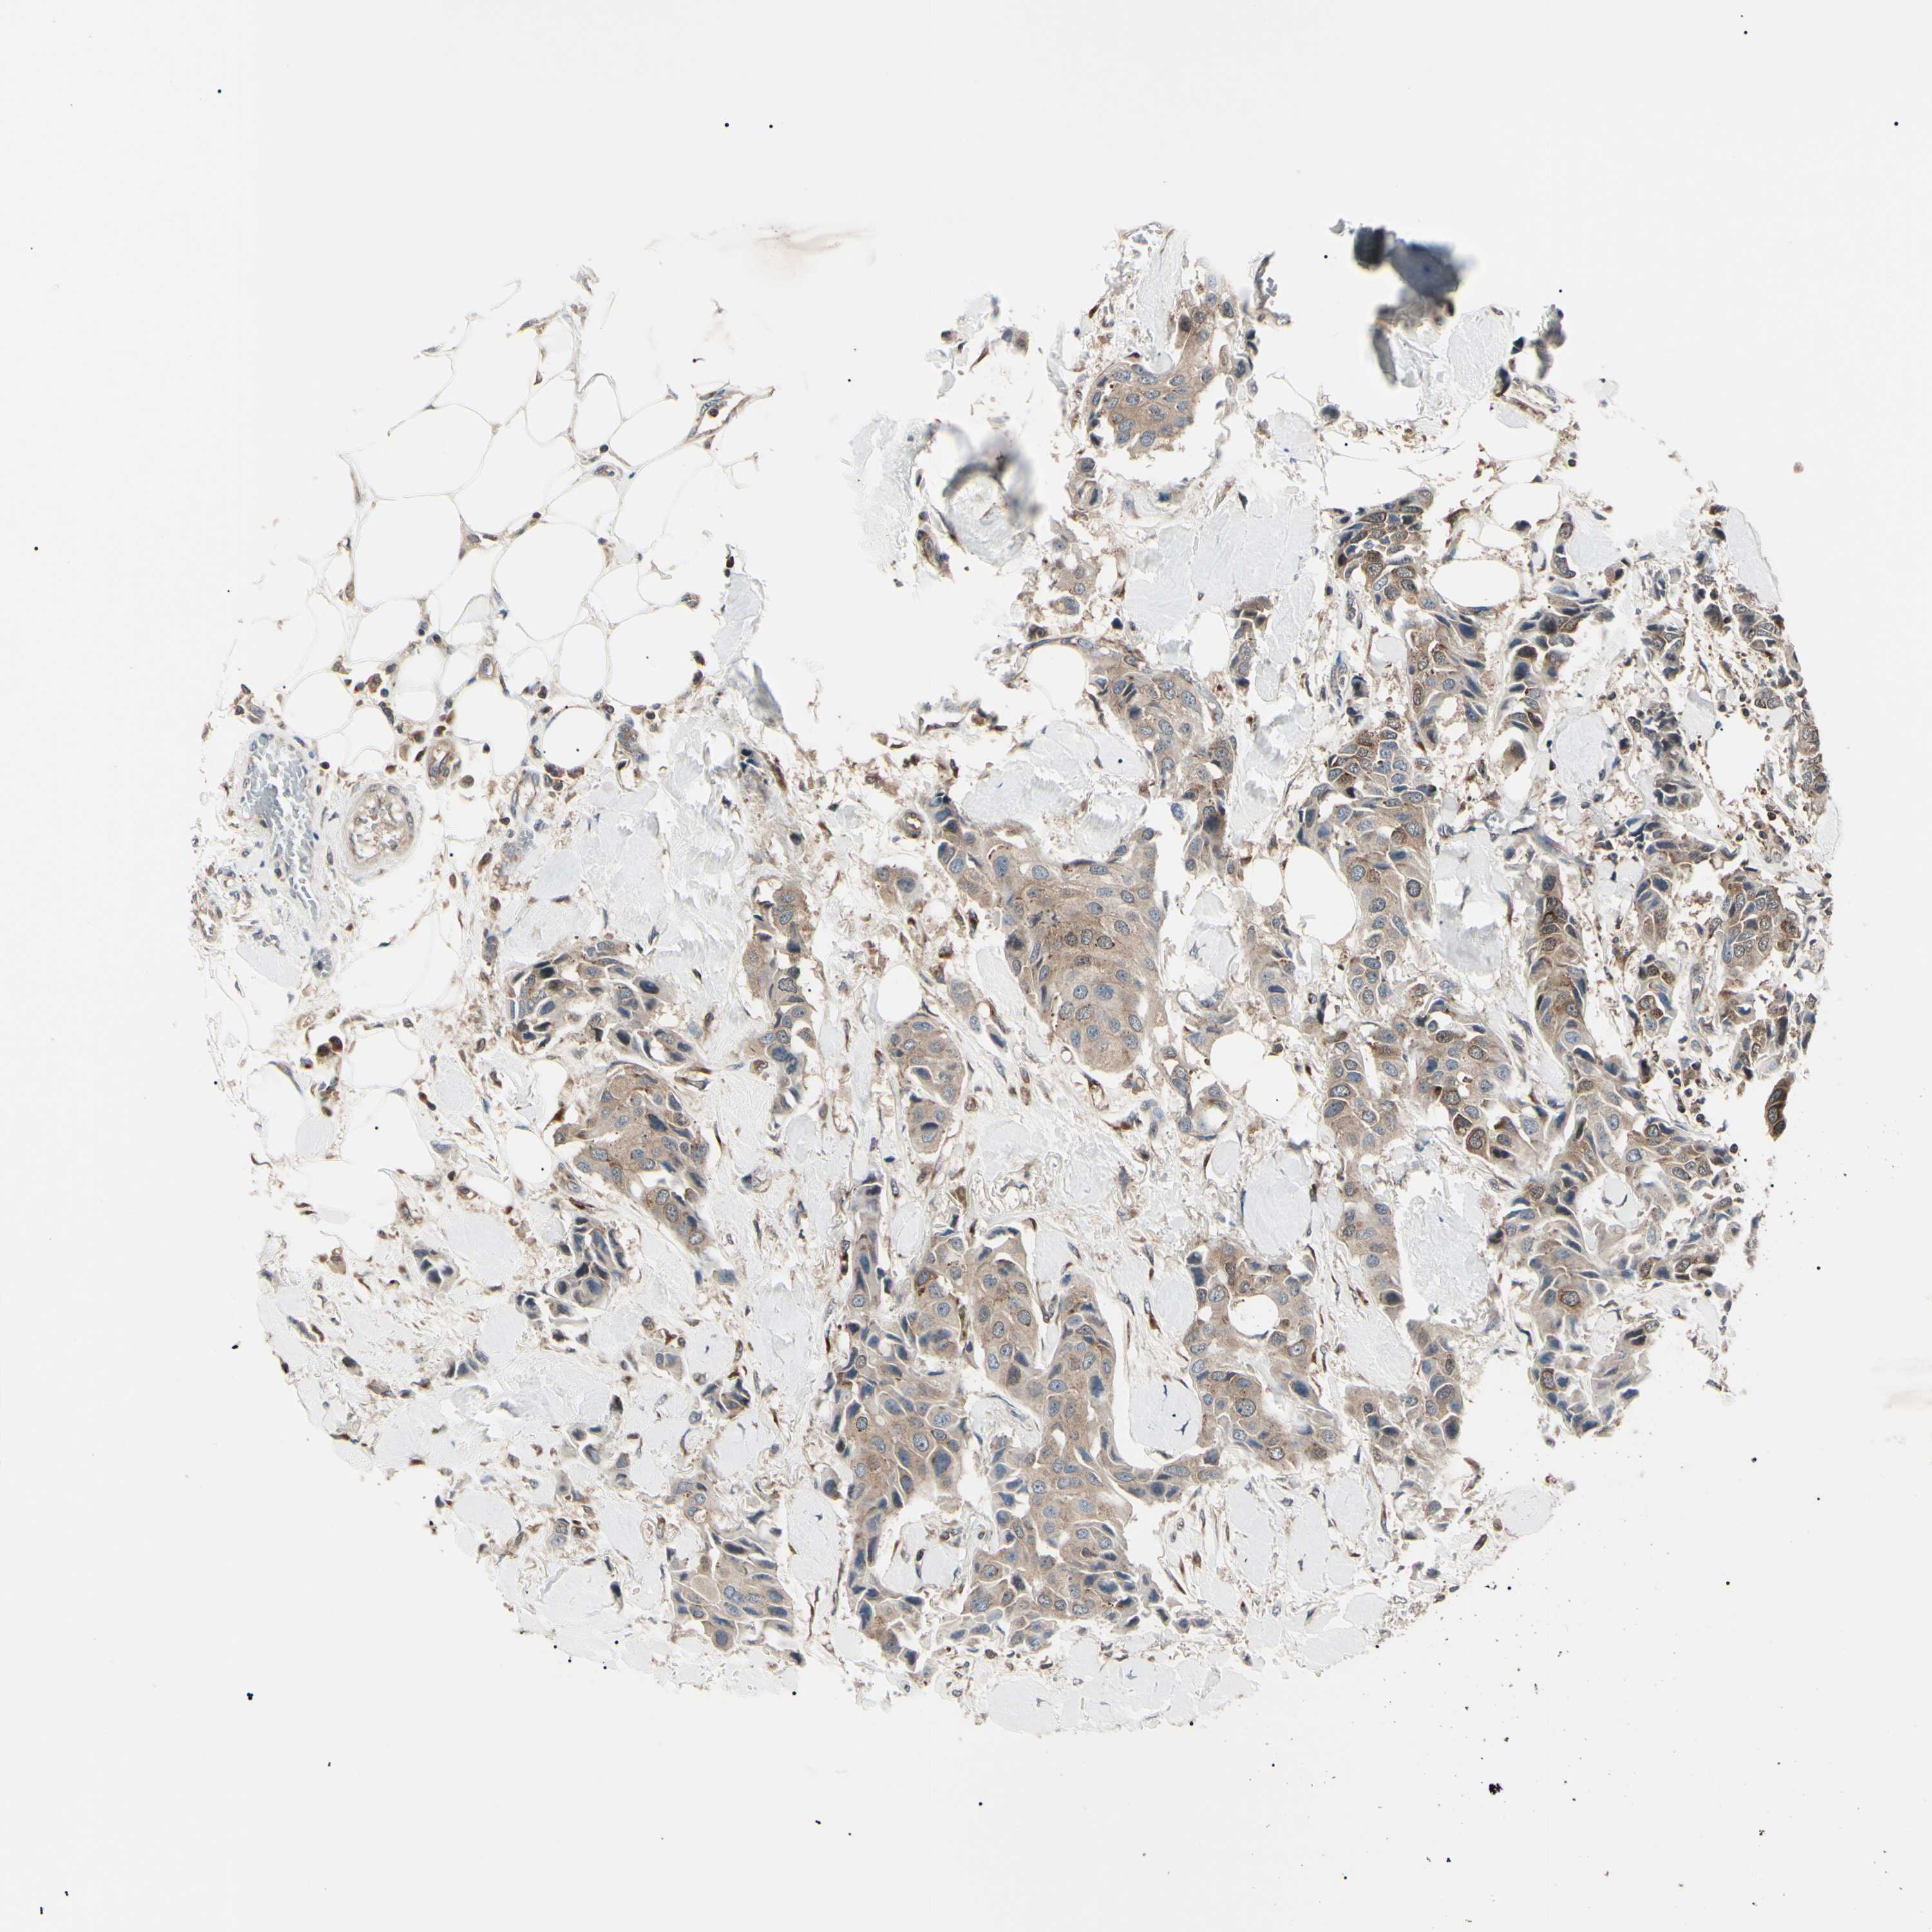

BRCA TCGA BRCA VALIDATION PROTEIN EXPRESSION